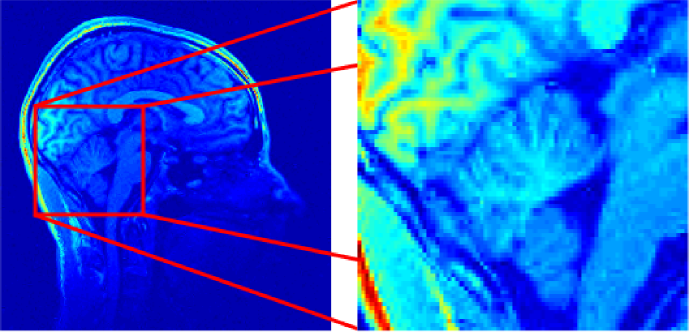

Let us now compare the reconstruction results using the TSP based method and the method proposed in the original CS-MRI paper [32]. These two sampling strategies are depicted in Fig. 8. For 2D independent drawings, we used the distribution providing the best reconstruction results in 2D, i.e. proportional to . The TSP-based schemes were designed by drawing city locations independently with respect to a distribution proportional to . According to Theorem 9 this is the correct way to reach distribution after joining the cities with constant speed along the TSP solution path. The experiments were performed with (see Fig. 2 (b)), and , since the latter yielded the best reconstruction results in the 3D independent VDS framework. We also compared these two continous schemes to 3D independent drawings with respect to a distribution proportional to .

| (a) | (b) |

![]() |

| (c) | (d) |

PSNR (dB)

| (a) (b) |

| (c) (d) |

|---|---|

Reconstruction results with an sampling rate are presented in Fig. 10, with a zoom on the cerebellum. The reconstruction quality using the proposed sampling scheme is better than the one obtained from classical CS acquisition and contains less artifacts. In particular, the branches of the cerebellum are observable with our proposed sampling scheme only. At higher sampling rate, we still observe less artifacts with the proposed schemes, as depicted in Fig. 11 with a sampling rate . Moreover, Fig. 9 shows that our proposed method outperforms the method proposed in [32] by up to 2dB. If one aims at reaching a fixed PSNR, we can increase by more than using the TSP based strategy. In other words, we could expect a substantial decrease of scanning time by using more advanced sampling strategies than those proposed until to now.